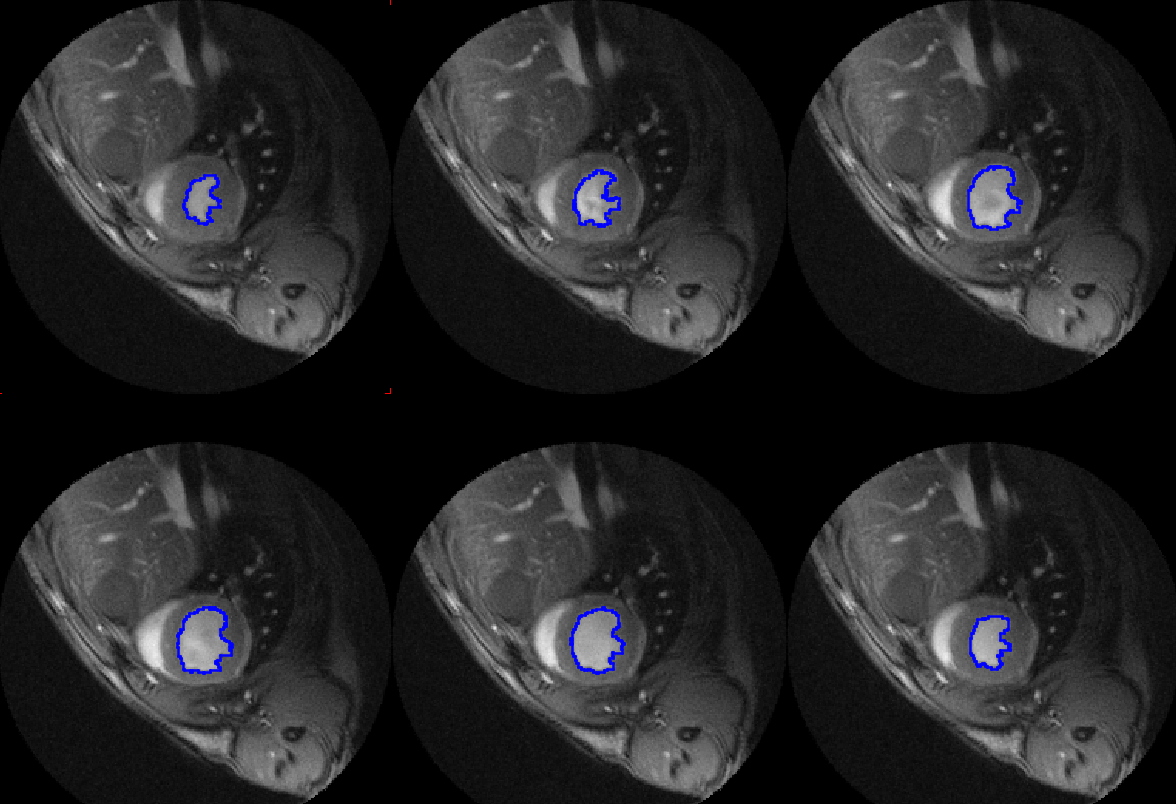

PCARDM Cardiac MR Analysis

P3D Extended Image Rendering

PAI Artificial Intelligence Framework

Extension tool for training of neural networks within the pmod environment.

Applications include segmentation, classification and image generation.

Recommended extension to PBAS, PNEURO or PCARDM